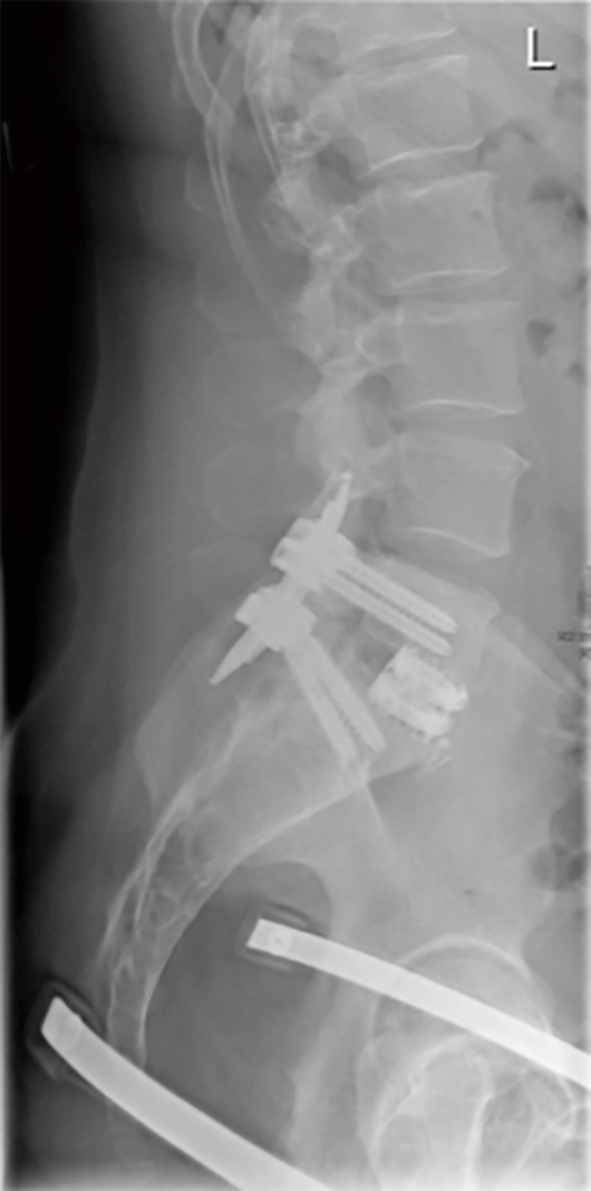

Lumbar Disc Degeneration: 2 Previous Spine Surgeries and Constant Low Back Pain from static.spineuniverse.com A herniated (slipped) disk occurs when all or part of a disk is forced through a weakened part of the disk. Ray spine lumbar #xray #xraylumbarspine #lsxray #sukoonphysicaltherapy #xrayreading #howtoreadlumbarspinexray #herniateddiscxray. A treatment plan may involve medication, physical therapy, and surgery. A process of trial and error is often necessary to find the right combination of treatments. This herniated disk pain is in the lowest part of the back. What is herniated disc in the lower back? Typical herniated disc diagnostic questions. Read about herniated disc (disc herniation of the spine) symptoms and treatment options, including exercises and surgery.

Disc herniation caused by a viscoelastic nucleus after total lumbar disc replacement—a case ... from cdn.amegroups.cn In many cases, they cause no symptoms and require no treatment. Lumbar herniated disc treatment may include extension exercises to help you ease pain while strengthening low back muscles. Application of radiation to produce a film or picture of a part of the body can show the structure of the vertebrae and the outline. A ruptured disc causes shooting pain in the cervical (neck), thoracic, or lumbar (back) region of the spine. Lower spine herniated disc topics. A herniated disk is a condition that can occur anywhere along the spine, but most often occurs in the lower back. Lower back pain is typically the first symptom of a lumbar disc herniation. For instance a herniated disc can cause nerve compression at the level of the disc, but also at here a 25 year old patient who presented with low back pain.